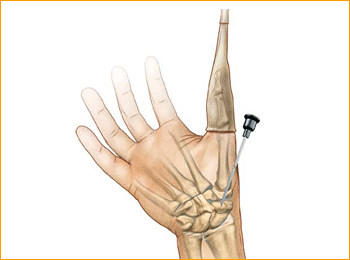

Volar Scaphoid Technique for 2.5 mm, 3 mm, 3.5 mm and 4 mm Headless Compression screws.

1. Approach and Needle Insertion

The procedure can be carried out using the volar traction approach or using a conventional volar type approach with the arm supine on a hand table. The volar traction approach facilitates reduction of a displaced fracture and permits arthroscopy to ensure accuracy of the reduction.

Fluoroscopy is used throughout.

The entry point is then located using a 12 or 14 gauge IV needle introduced on the antero-radial aspect of the wrist just radial to and distal to the scaphoid tuberosity. This serves as a trochar for the guide wire and is a directional aid to establish a central path along the scaphoid. The needle is then insinuated into the scaphotrapezial joint, tilted into a more vertical position and the position is checked on the under image

intensifier. By gently levering on the trapezium this maneuver brings the distal pole of the scaphoid more radial and thus ultimately facilitates screw insertion. The entry point should be approximately 1/3 the way across the scaphoid from the tuberosity in the A/P plane and central in the lateral plane.